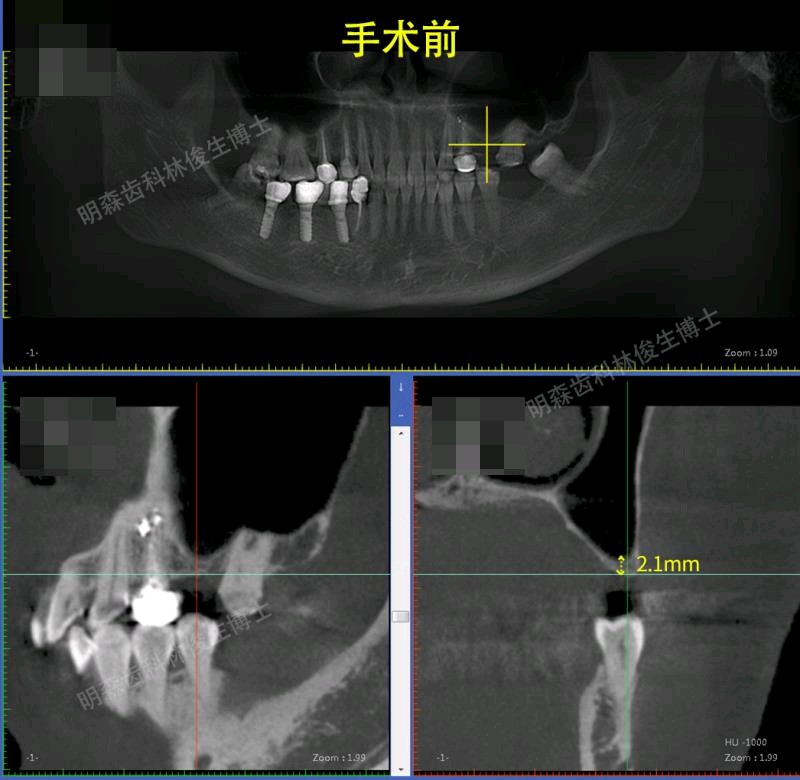

辅助检查:cbct示:25,27牙槽骨高度不足,36,37牙槽骨高度尚足

治疗方案:1.建议13-23贴面+14,15,33-43贴面修复,上前牙邻面龋补牙。 2.38.48拔除 3.24-26连冠修复,14.15换全瓷冠 4.25,27外提+植骨+种植,36,37种植修复(ITI钛锆)5.17充填治疗